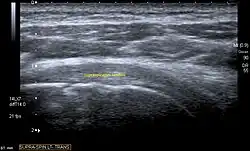

Ultrasound

There are several advantages of ultrasound. It is relatively cheap, does not emit any radiation, is accessible, is capable of visualizing tissue function in real time, and allows the performance of provocative maneuvers in order to replicate the patient’s pain.[28] Those benefits have helped ultrasound become a common initial choice for assessing tendons and soft tissues. Limitations include, for example, the high degree of operator dependence and the inability to define pathologies in bones. One also has to have an extensive anatomical knowledge of the examined region and keep an open mind to normal variations and artifacts created during the scan.[29]

After the introduction of high-frequency transducers in the mid-1980s, ultrasound has become a conventional tool for taking accurate and precise images of the shoulder to support diagnosis.[31][32][33][34][35]

Adequate for the examination are high-resolution, high-frequency transducers with a transmission frequency of 5, 7.5, and 10 MHz. To improve the focus on structures close to the skin an additional "water start-up length" is advisable. During the examination the patient is asked to be seated, the affected arm is then adducted and the elbow is bent to 90 degrees. Slow and cautious passive lateral and/or medial rotations have the effect of being able to visualize different sections of the shoulder. In order to also demonstrate those parts which are hidden under the acromion in the neutral position, a maximum medial rotation with hyperextension behind the back is required.[36]

Longitudinal ultra sonography of the supraspinatus tendon

Transversal ultra sonography of the supraspinatus tendon